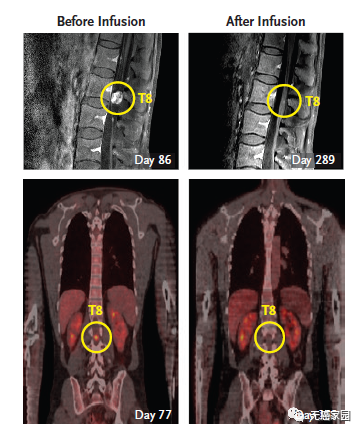

2016年12月,NEJM曾报道过1例利用CAR-T技术治疗脑胶质瘤的案例。一名50岁的男性,确诊为高级别脑胶质瘤,先后做了手术、放疗、替莫唑胺化疗等常规治疗,6个月后疾病复发。这时他参加了一项临床试验,接受靶向IL13Rα2的CAR-T治疗。不过这个疗法,有些“惊悚”。

主管医生通过核磁共振检查发现:这位病友脑部有5个病灶;因此,先通过手术切掉其中的三个大的,还剩下两个较小的由于位置深,无法切除。主管医生就给他的病灶处直接插了一个管子,然后通过这个管子,把CAR-T细胞打了进去,分3个批次,进行了多次的细胞回输。最终,肿瘤完全消失,疗效维持了8个月左右。